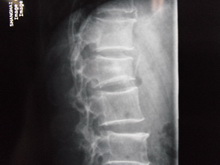

腰椎压缩型骨折

一、胸腰椎压缩骨折治疗组

本器材的原理:通过患者胸锁骨与耻骨联合处为支撑力点,用《可调式固定支具(腰椎型)》中提拉装置,提升腰部后面的固定带。把契形骨折通过腰部固定带直接提拉出正常范围内腰部的生理弧度。使胸腰椎契形状骨折,逐步改变弧度,从而使骨折部位复位。一般骨折二周内可以逐步通过提拉装置,每隔三天提拉一次,直至坐稳弧度在正常范围内为止。